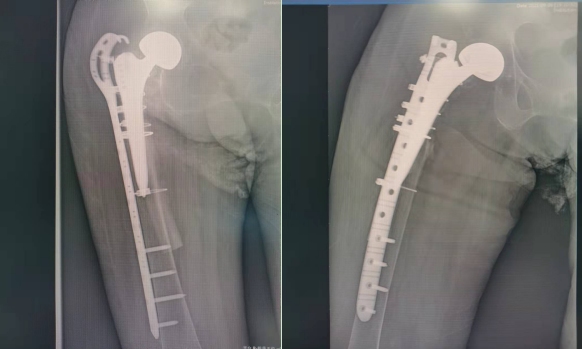

病历分享如下:患者,老年女性,86岁,2021年6月12日入院,诊断:1、假体周围骨折(右);2、人工股骨头置换术后(双侧);3、重度骨质疏松;4、肺炎;5、高血压级(极高危组);6、贫血;7、泌尿道感染;8、隐匿性冠状动脉粥样硬化性心脏病;9、心功能III级;10、胸腔积液;11、高钾血症;12、低蛋白血症;13、甲状腺功能亢进症;14、十二指肠溃疡;15、胸腔积液。患者住骨关节创伤科后,多科室合作,通过绿色通道,很快完成术前检查,手术麻醉科白艳艳主任团队主持术前麻醉评估,顺利完成手术麻醉,骨关节创伤科李峰主任主刀完成手术,术后转重症监护室,由陈璞莹主任及李斌副主任保驾护航,渡过危险期,出监护室后转保健病房,由魏文玺主任综合术后管理,治疗复杂内科疾病,最终患者顺利出院,得到较好的诊疗效果。

术后X线片

术后3个月复查X线片